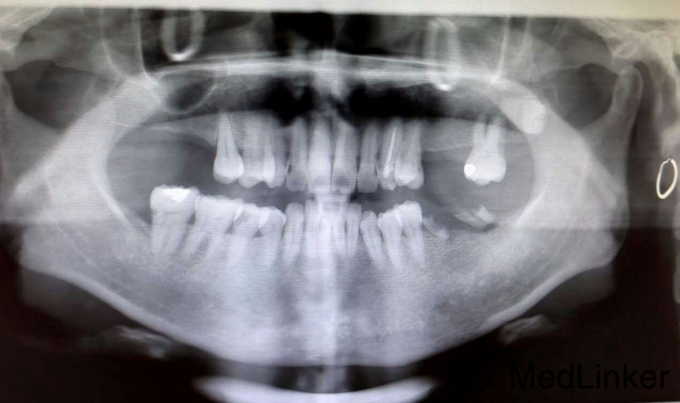

患者女49岁 后牙缺失欲种植

后牙缺失欲种植